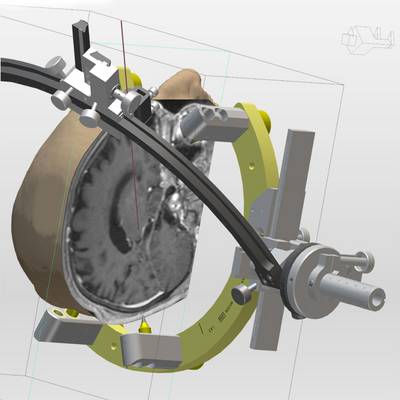

Die Möglichkeit einer schnellen Generierung von 3D Ansichten des Patientenschädels hilft bei der Verifikation der Zielpunktplanung im Zuge der THS. Durch Projektion des verwendeten Stereotaxie-Systems bekommt der Anwender eine realistische Darstellung über Anordnung und Auswirkung der Trajektorie-Planung auf den Systemaufbau.

Das Generieren von Volumen gestattet die Visualisierung von Strukturen, deren Bedeutung für die Zielpunktverifikation bei der THS groß ist. Ob nun Bild für Bild die gewünschte Struktur markiert oder per Softwarefunktion anhand von Schwellwerten automatisch erkannt wird, schlussendlich kann jedes Volumina als Objekt in der 3D-Visualisierung dargestellt werden.

- 3D-Simulation auf Basis von Patientendaten

- Visualisierung von Trajekten anhand BenGun-Anordnung